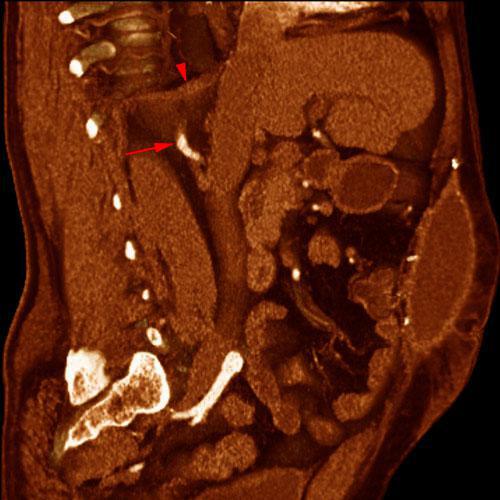

Arterias renales accesorias